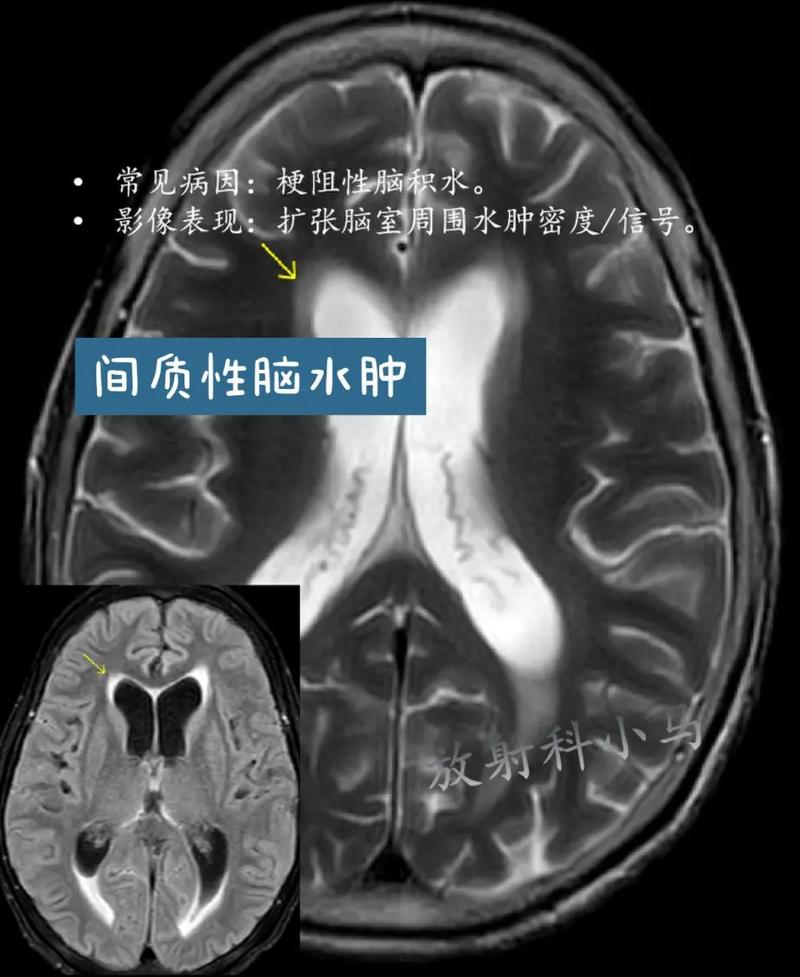

脑积水的症状

脑积水是由于脑脊液循环通路发生阻塞,导致脑脊液在脑室系统内过多积聚,使脑室扩大,从而压迫周围正常的脑组织,脑积水的症状发展通常比较缓慢,呈进行性加重,但急性脑积水(如脑出血后突然阻塞)则发展迅速。

脑积水的症状主要与颅内压增高脑组织受压有关,具体表现因发病年龄和病情急缓而异。